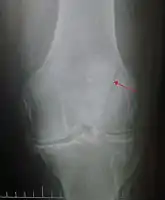

Diagnosis

Diagnosis is based on symptoms and examination, which typically reveals a swollen knee with reduced movement and a tender kneecap.[5] A fracture is subsequently confirmed with X-rays usually taken from different angles.[3] In children an MRI may be required.[3]